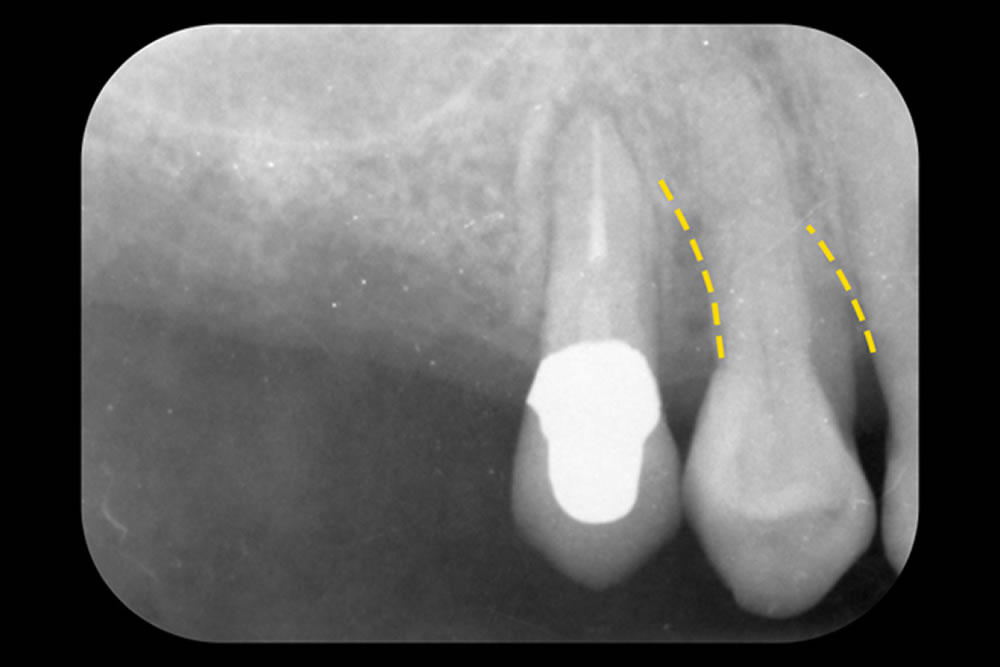

こちらの患者さまは、右上の小臼歯において、歯の前後に深い骨の欠損(垂直性骨欠損)がみられました。これらの欠損は歯周病の進行によって引き起こされるもので、歯を支える骨が溶けてしまった状態です。

治療では、「M-MINST(Modified Minimally Invasive Surgical Technique)」という、できるだけ歯ぐきへのダメージを抑えて治療を行う方法を採用しました。今回は、連続した骨欠損だったため、2本の歯をまとめて処置できるように、連続した切開線で手術を行いました。